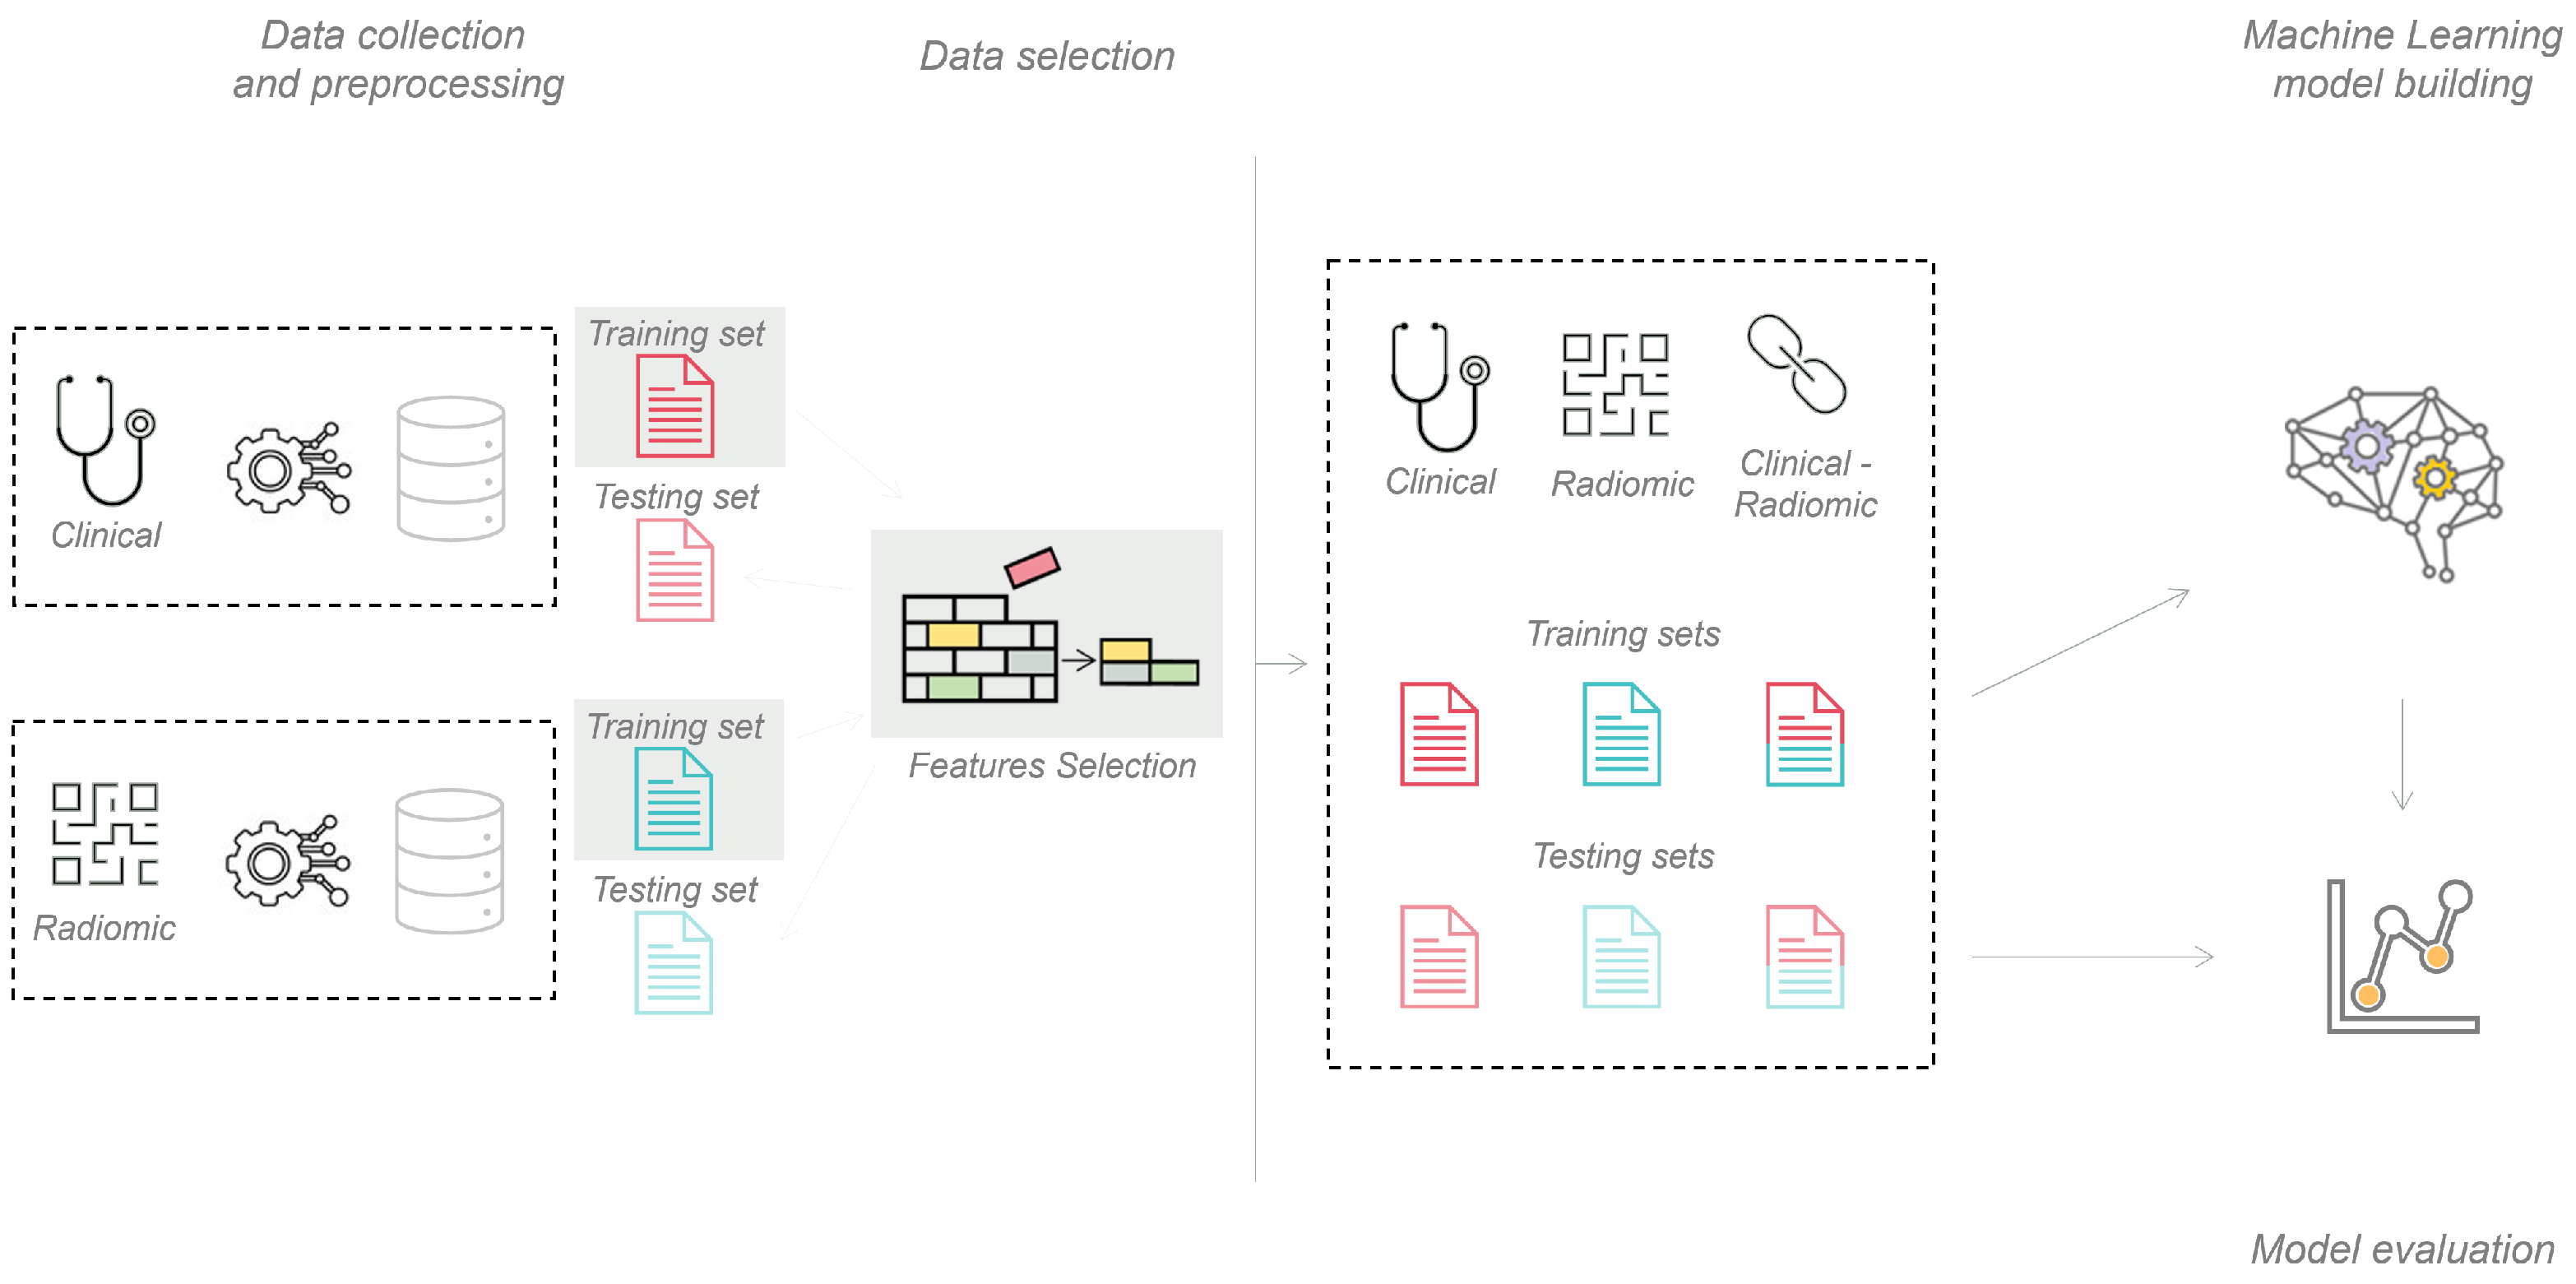

2.4. Machine Learning Pipeline

2.5. Deep Learning Pipeline